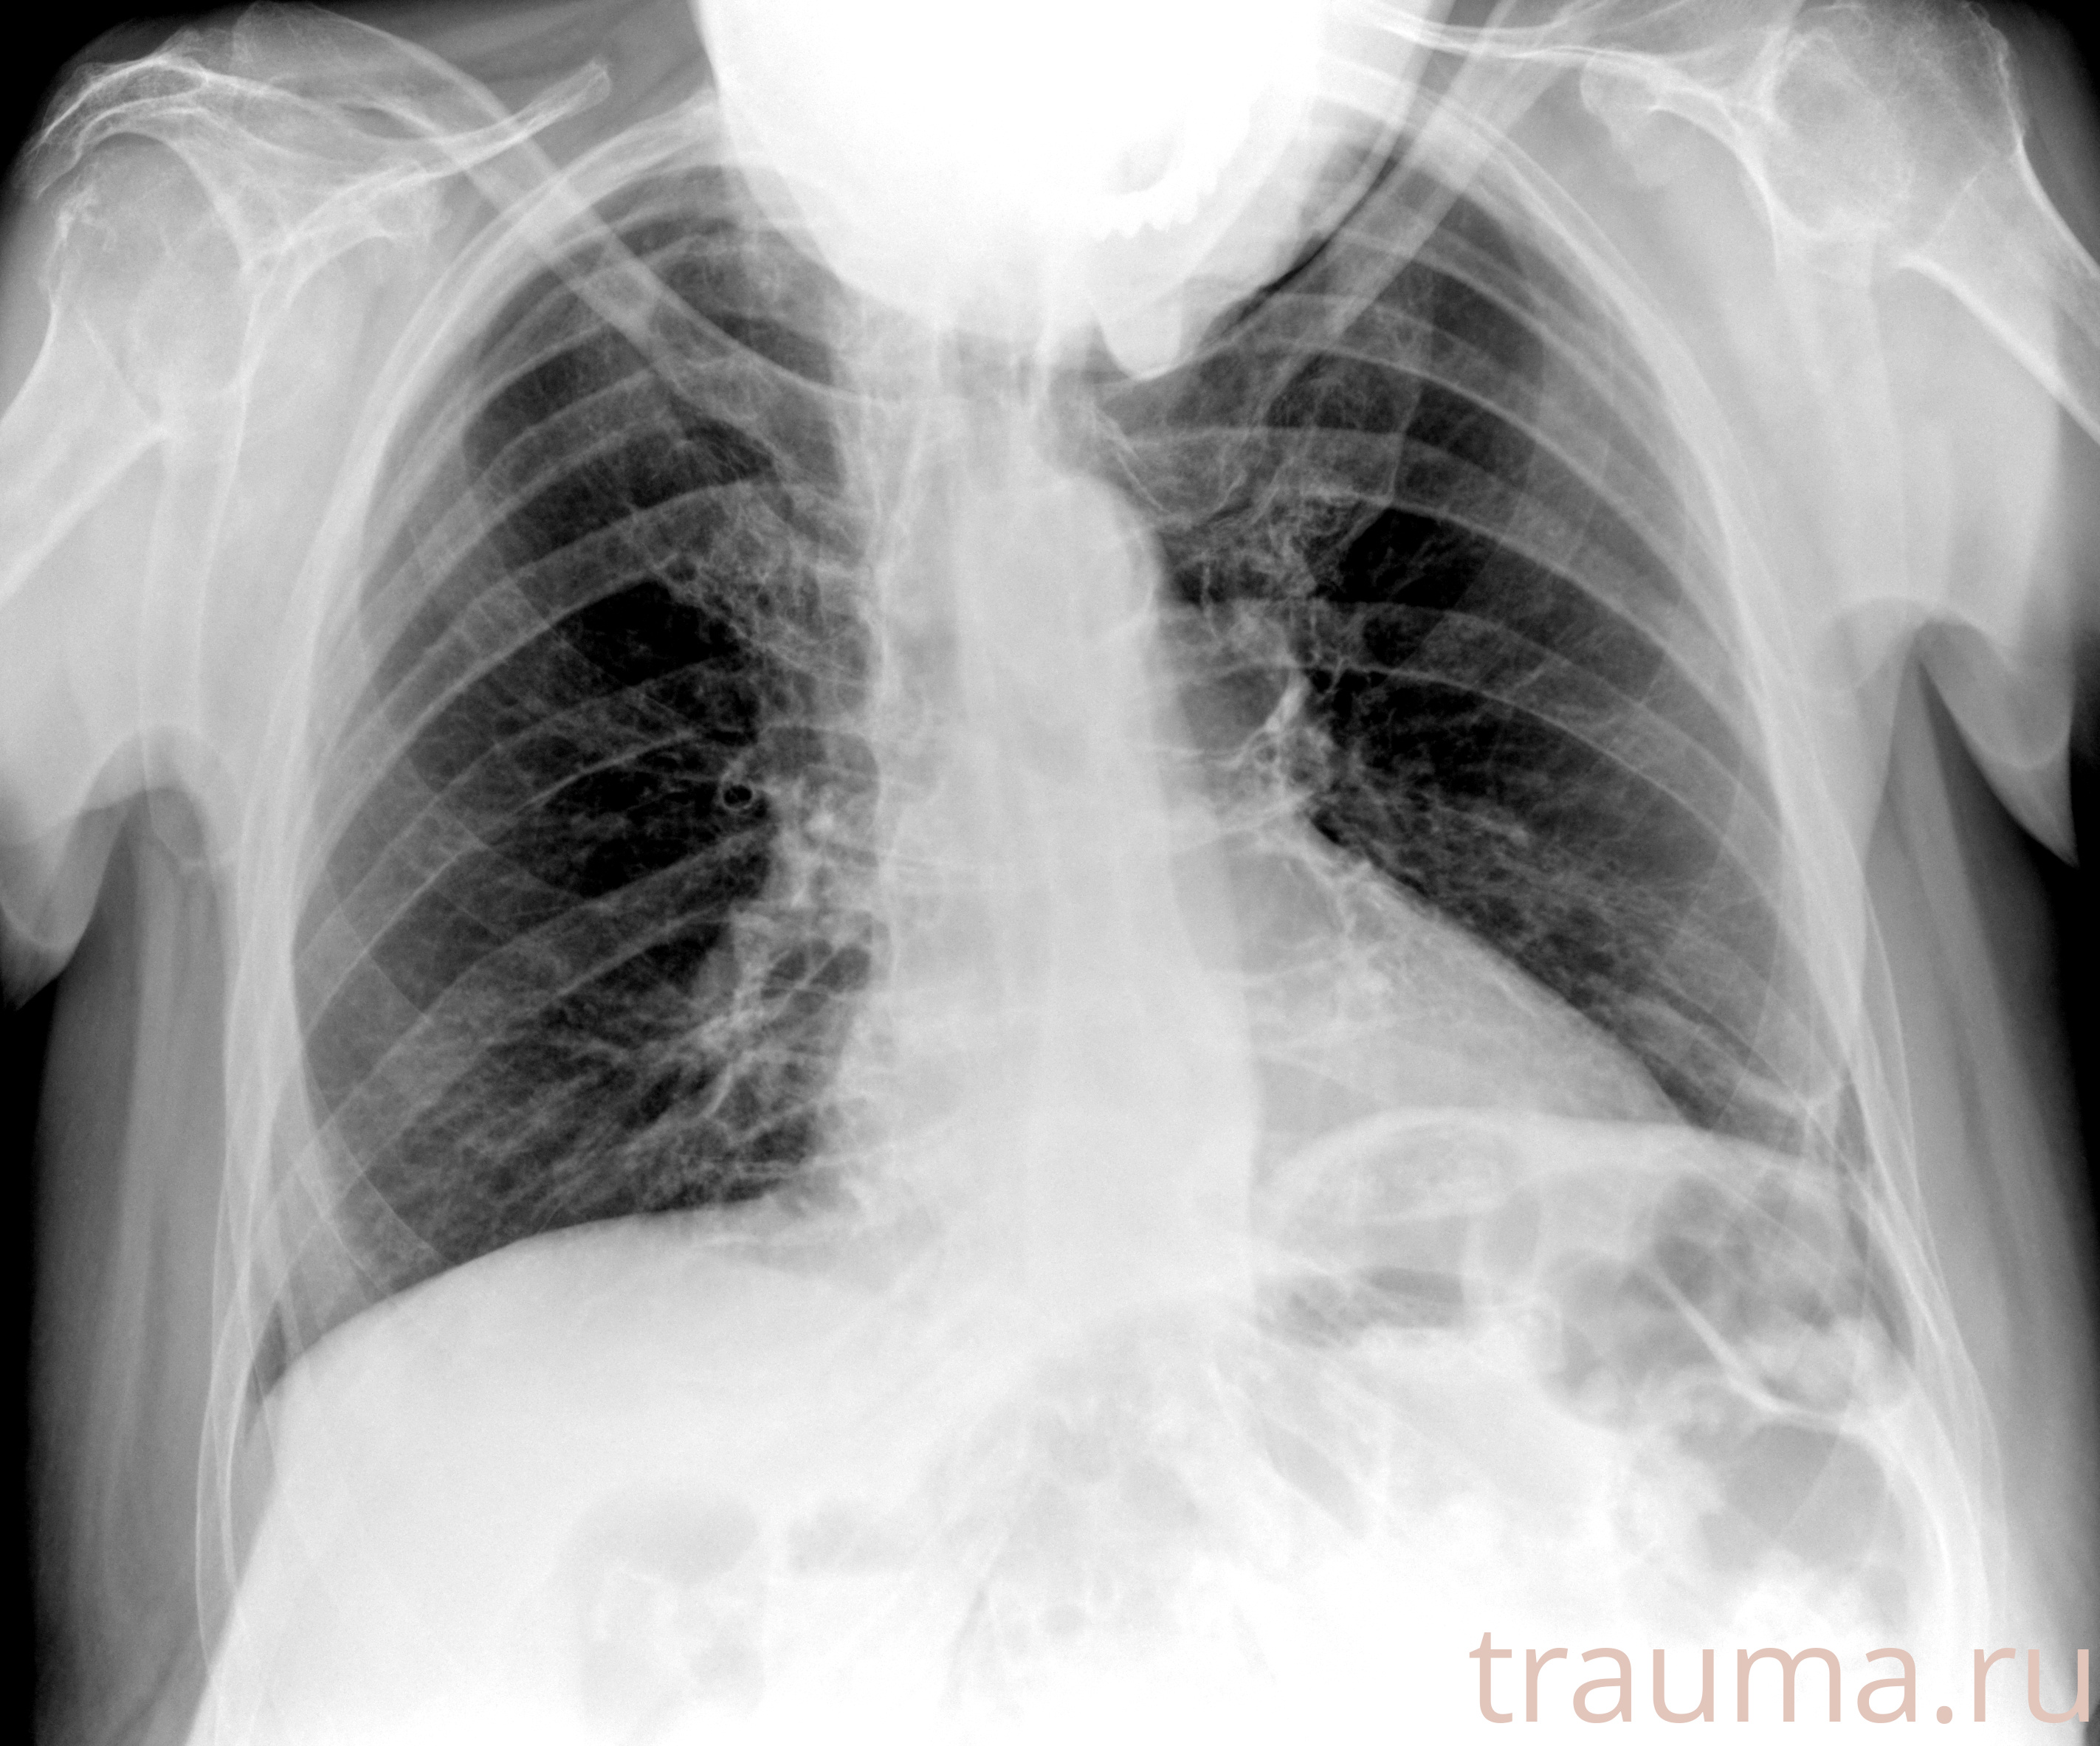

Рентгенограммы

Рентген на дому: по вашему адресу приезжает врач-рентгенолог, травматолог-ортопед с мобильным рентгеновским аппаратом, проводит диагностику травмы или заболевания, делает необходимые рентгенограммы, дает рекомендации по дальнейшему лечению. Получить качественные снимки в домашних условиях возможно благодаря уникальной методике, разработанной МосРентген Центром для института  Склифосовского